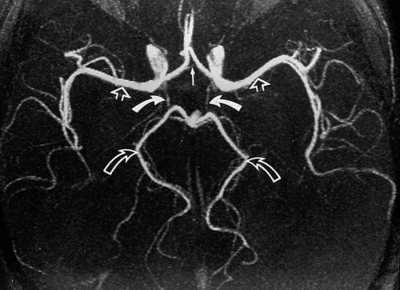

De façon physiologique, les artères communicantes postérieures ne sont pas très larges, y'a vraiment très peu de sang qui y passe (comme tu peux le voir sur ces deux angiographies) :